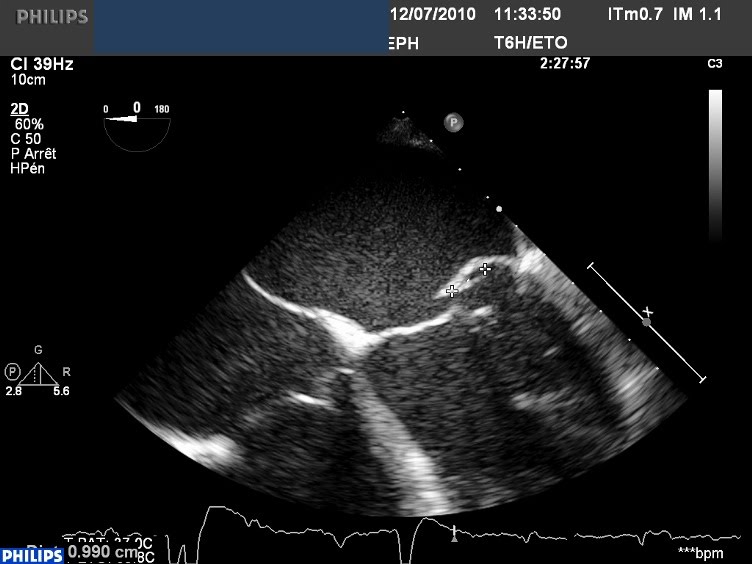

Il s’agit d’une IM massive sur prolapsus de P2 avec rupture de cordage. Jusque là, tout va bien.

Le jet est très directionnel, plaqué vers le SIA grâce à « l’effet coanda » le magnifique (à ne pas confondre avec Conan le barbare, qui n’a que très peu d’effet sur les jets d’IM). Jusque là, tout va bien.

Mais, en y regardant de plus près, le flux d’IM se jette sans vergogne dans une toute petite CIA, en position d’ostium secundum, avec une vitesse du jet de CIA de plus de 4 m/sec!